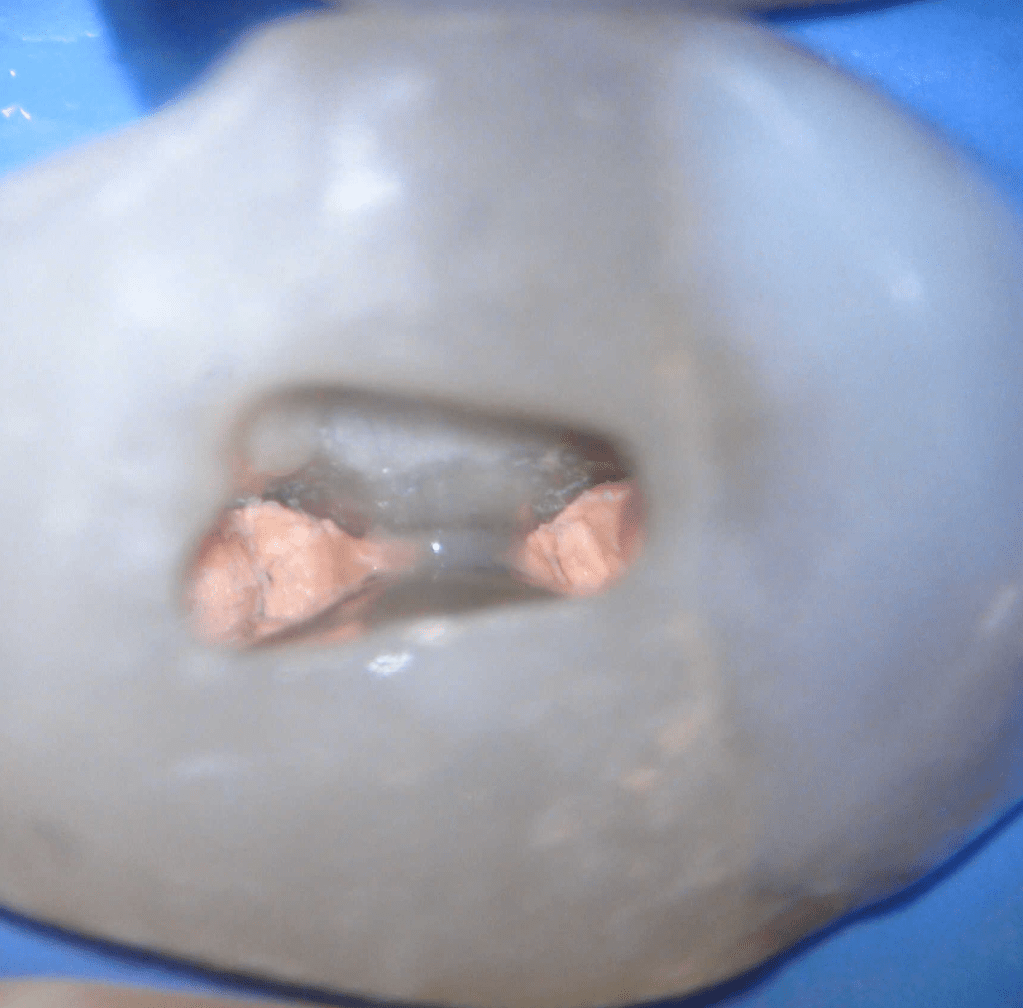

Pulpotomía biodentine + reco preendio